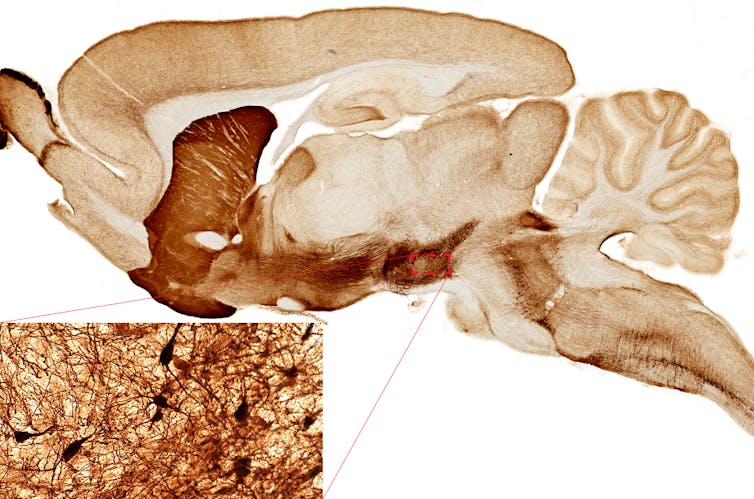

El movimiento del cuerpo humano tiene su origen en circuitos neurales que estimulan la contracción de los músculos del cuerpo. En distintos centros neurales de nuestro cerebro y de forma jerárquica se toman decisiones para elaborar y ejecutar un programa motor. El sistema de control del movimiento cerebral incluye tanto actividades motoras rutinarias, como caminar, hasta movimientos más elaborados, como tocar el piano, bailar o lanzar un triple.

En el primer nivel en la jerarquía de la toma de decisiones de movimiento encontramos la corteza cerebral, que da el pistoletazo de salida a la elaboración de un plan motor. La orden transcurre por diversas estructuras cerebrales como las del tronco del encéfalo, cuyas redes neurales ajustan el plan motor. Finalmente, el estímulo definitivo dirigido a la musculatura responsable del movimiento parte principalmente de las redes neurales de la médula espinal.

Al administrar bloqueantes de la acción dopaminérgica mediada por los receptores D1 se observó que el tiempo de actividad física resistido por los roedores en la rueda disminuía significativamente. De esta forma, se determinó que estructuras cerebrales como las del cuerpo estriado y de otras regiones del cerebro participarían en la modulación de la capacidad de ejercicio, y que esta depende a su vez de la acción dopaminérgica.